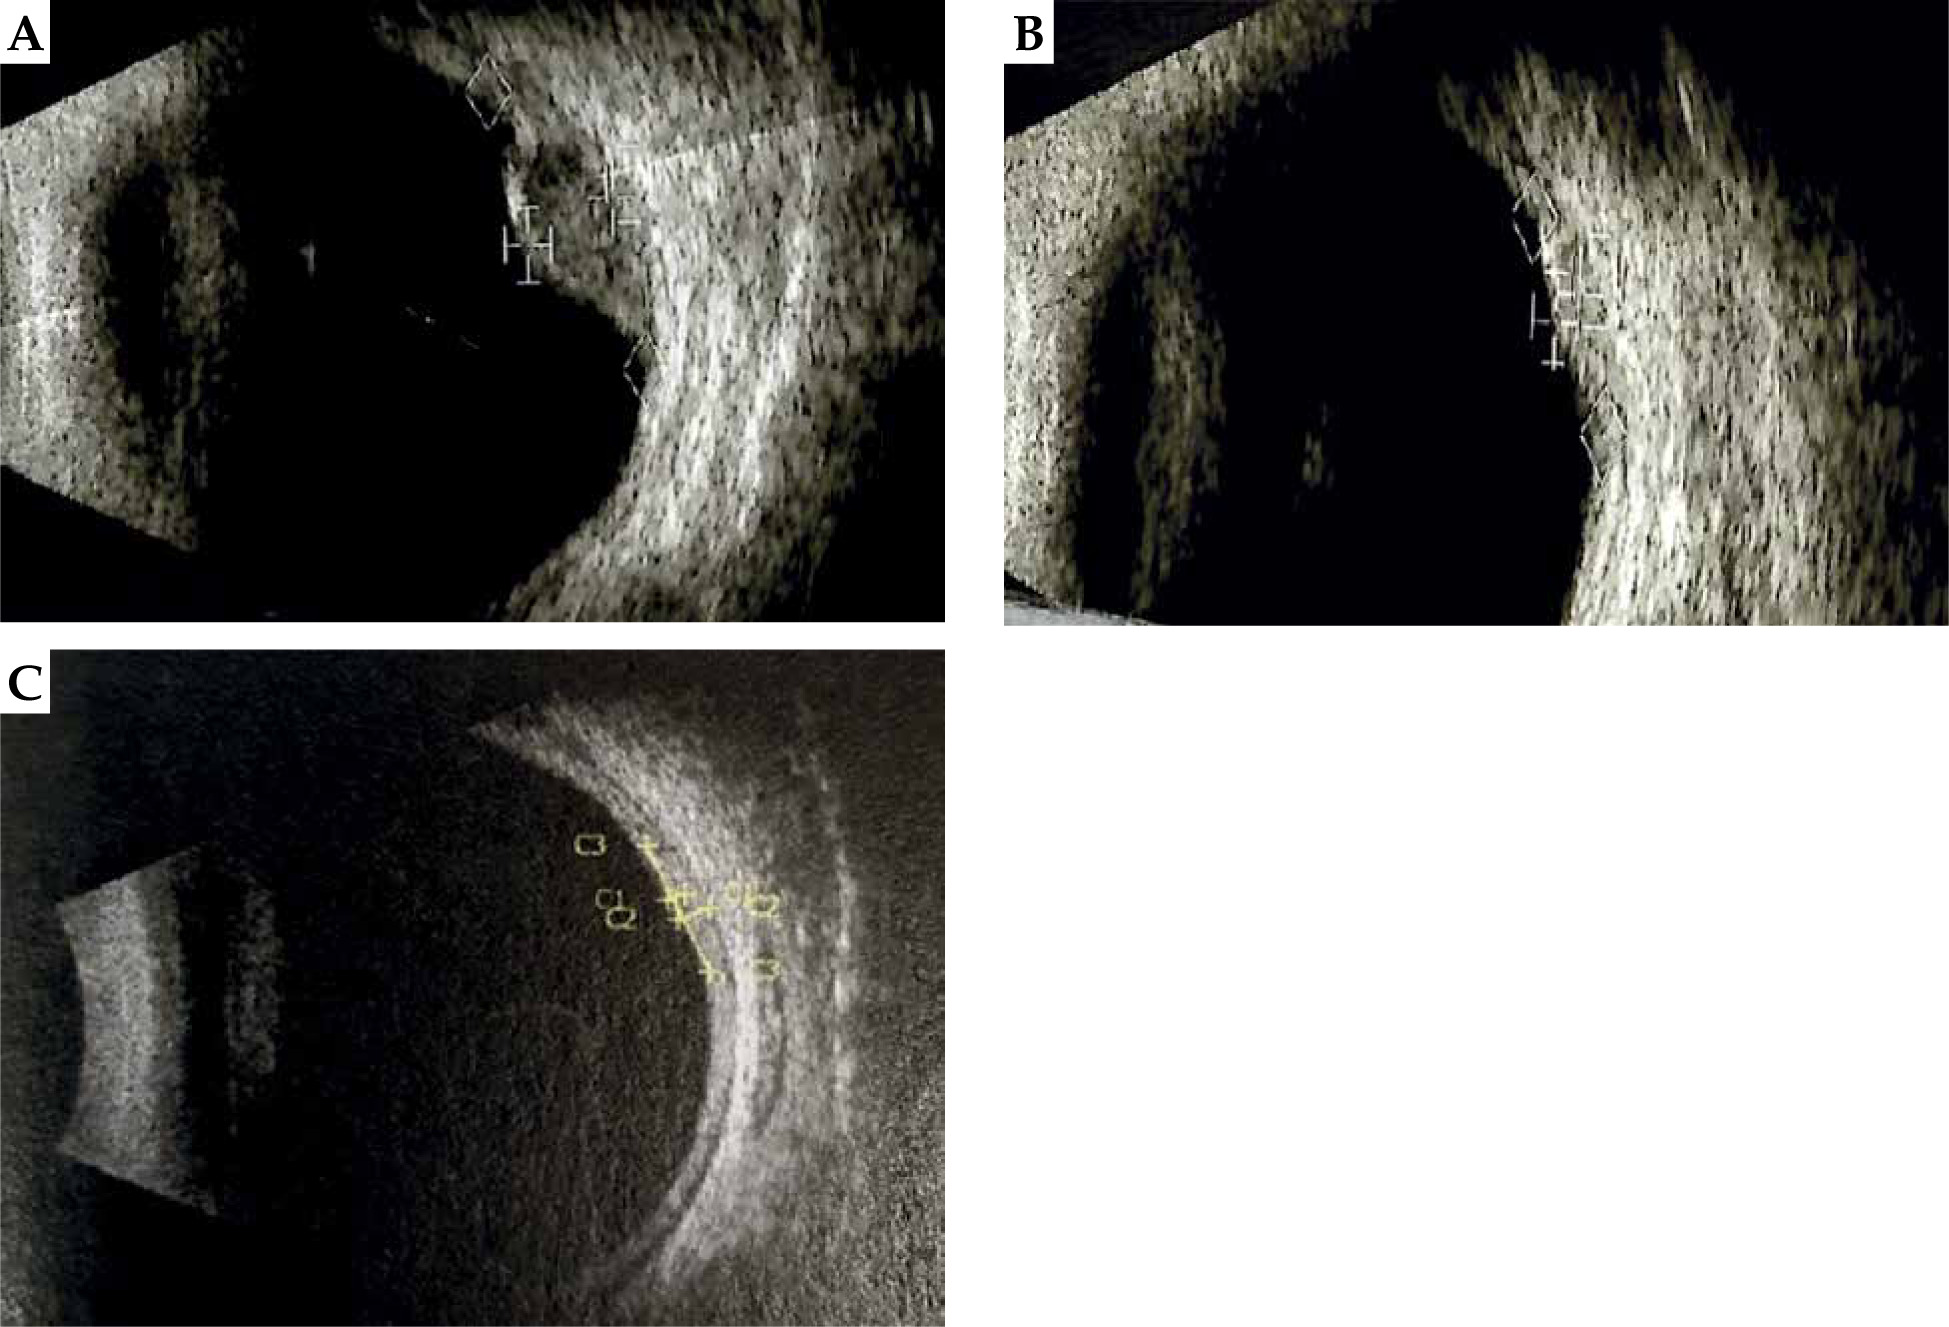

Fig. 2

Picture of the eye fundus before (A) and four years after treatment (B) of large uveal melanoma using applicator displacement

In 5 patients (56%) treated with the ophthalmic applicator displacement method, a positive result, i.e., local control of the tumor was achieved. In the remaining 4 cases (44%), a local recurrence developed. Within the follow-up period (range, 6-37 months; mean, 17.5 months), 4 patients underwent enucleation: 3 cases due to tumor progression and 1 due to radiation complications, despite the positive results of local treatment. One patient with recurrence was qualified for a secondary 106Ru brachytherapy with transpupillary thermo-therapy. As a result of the second treatment, a positive local result of the therapy was obtained. In the 4 remaining patients with positive local results after the first treatment, no recurrence of uveal melanoma was observed within the follow-up period (range, 7-62 months; mean, 23.1 months). Results presented in Figures 1 and 2 show the positive effects of treatment of the patient, who has been under control for the longest time, i.e., over 6.6 years.